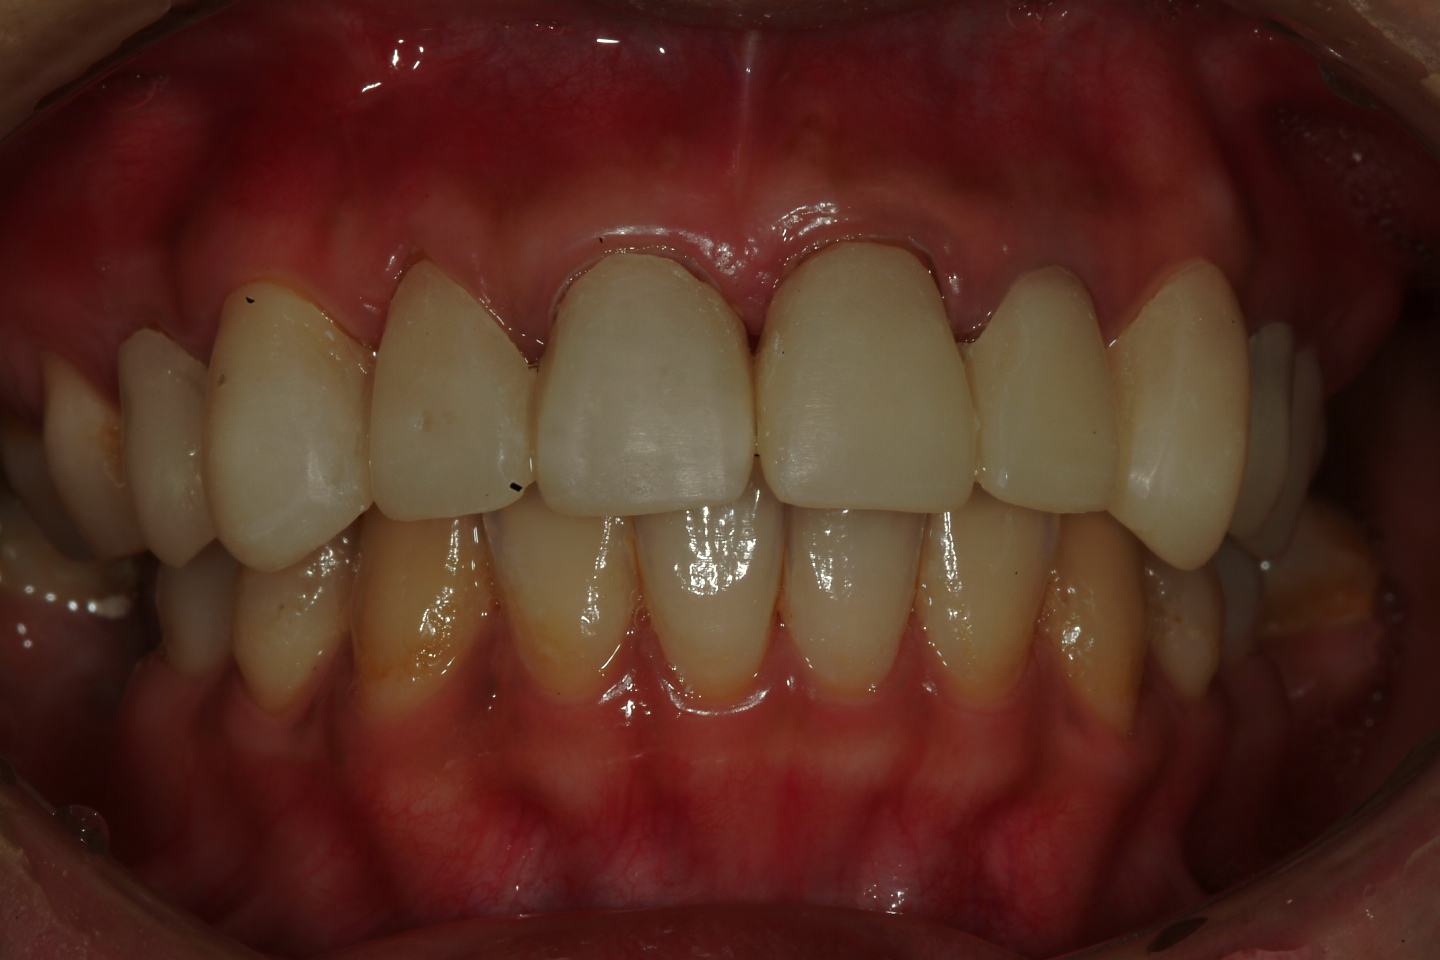

圖二 |

本病例的治療計畫方式為:

一、將根尖病變之牙齒 ,重新根管治療

二、製作根管內釘住 , 以支持假牙

三、上咬合器後 , 與病患討論未來假牙外型(圖三)

圖三 |